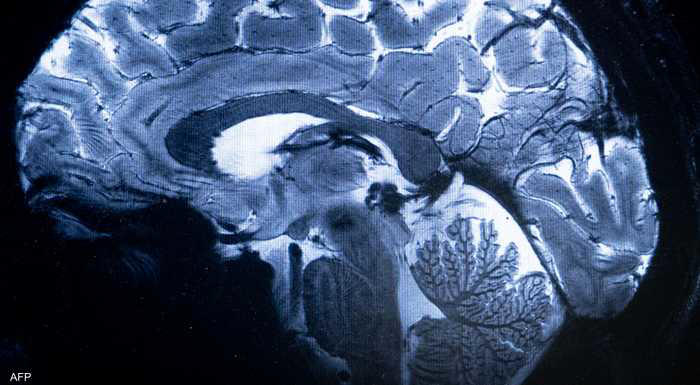

دراسة جديدة: مخ الانسان يغتسل أثناء النوم

سرايا - على مدار عقود طويلة، ظل العلماء يفكرون في مشكلة أساسية، وهي كيف يتخلص مخ الانسان من النفايات التي يفرزها أثناء العمل والتفكير طوال اليوم، والتي تتضمن بروتينات وجزيئات زائدة قد تتحول إلى مواد سامة في حالة عدم التخلص منها، ومن بينها بروتينات الأميلويد بيتا وتاو التي تعتبر من المسببات الأساسية لمرض الزهايمر.